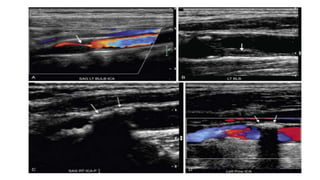

Pitfalls: Pathology • TortuousCarotid Artery When the carotid arteries are tortuous, most commonly in elderly patients, PSV can be elevated without an underlying stenosis. This is due in part to a true increase in PSV as the blood accelerates around the curves but is also likely due to difficulty in assigning a correct Doppler angle along the curved vessel, which results in an overestimation of PSV due to incorrect Doppler angle

• #33 Tortuous ICA. A, Color Doppler image demonstrates a tortuous right ICA. B, Duplex Doppler tracing demonstrates a PSV of 186 cm/sec. By SRU criteria, this corresponds to a 50% to 69% stenosis. However, no stenosis was noted on gray-scale or color Doppler imaging. Increased PSV is due to tortuosity of the vessel.